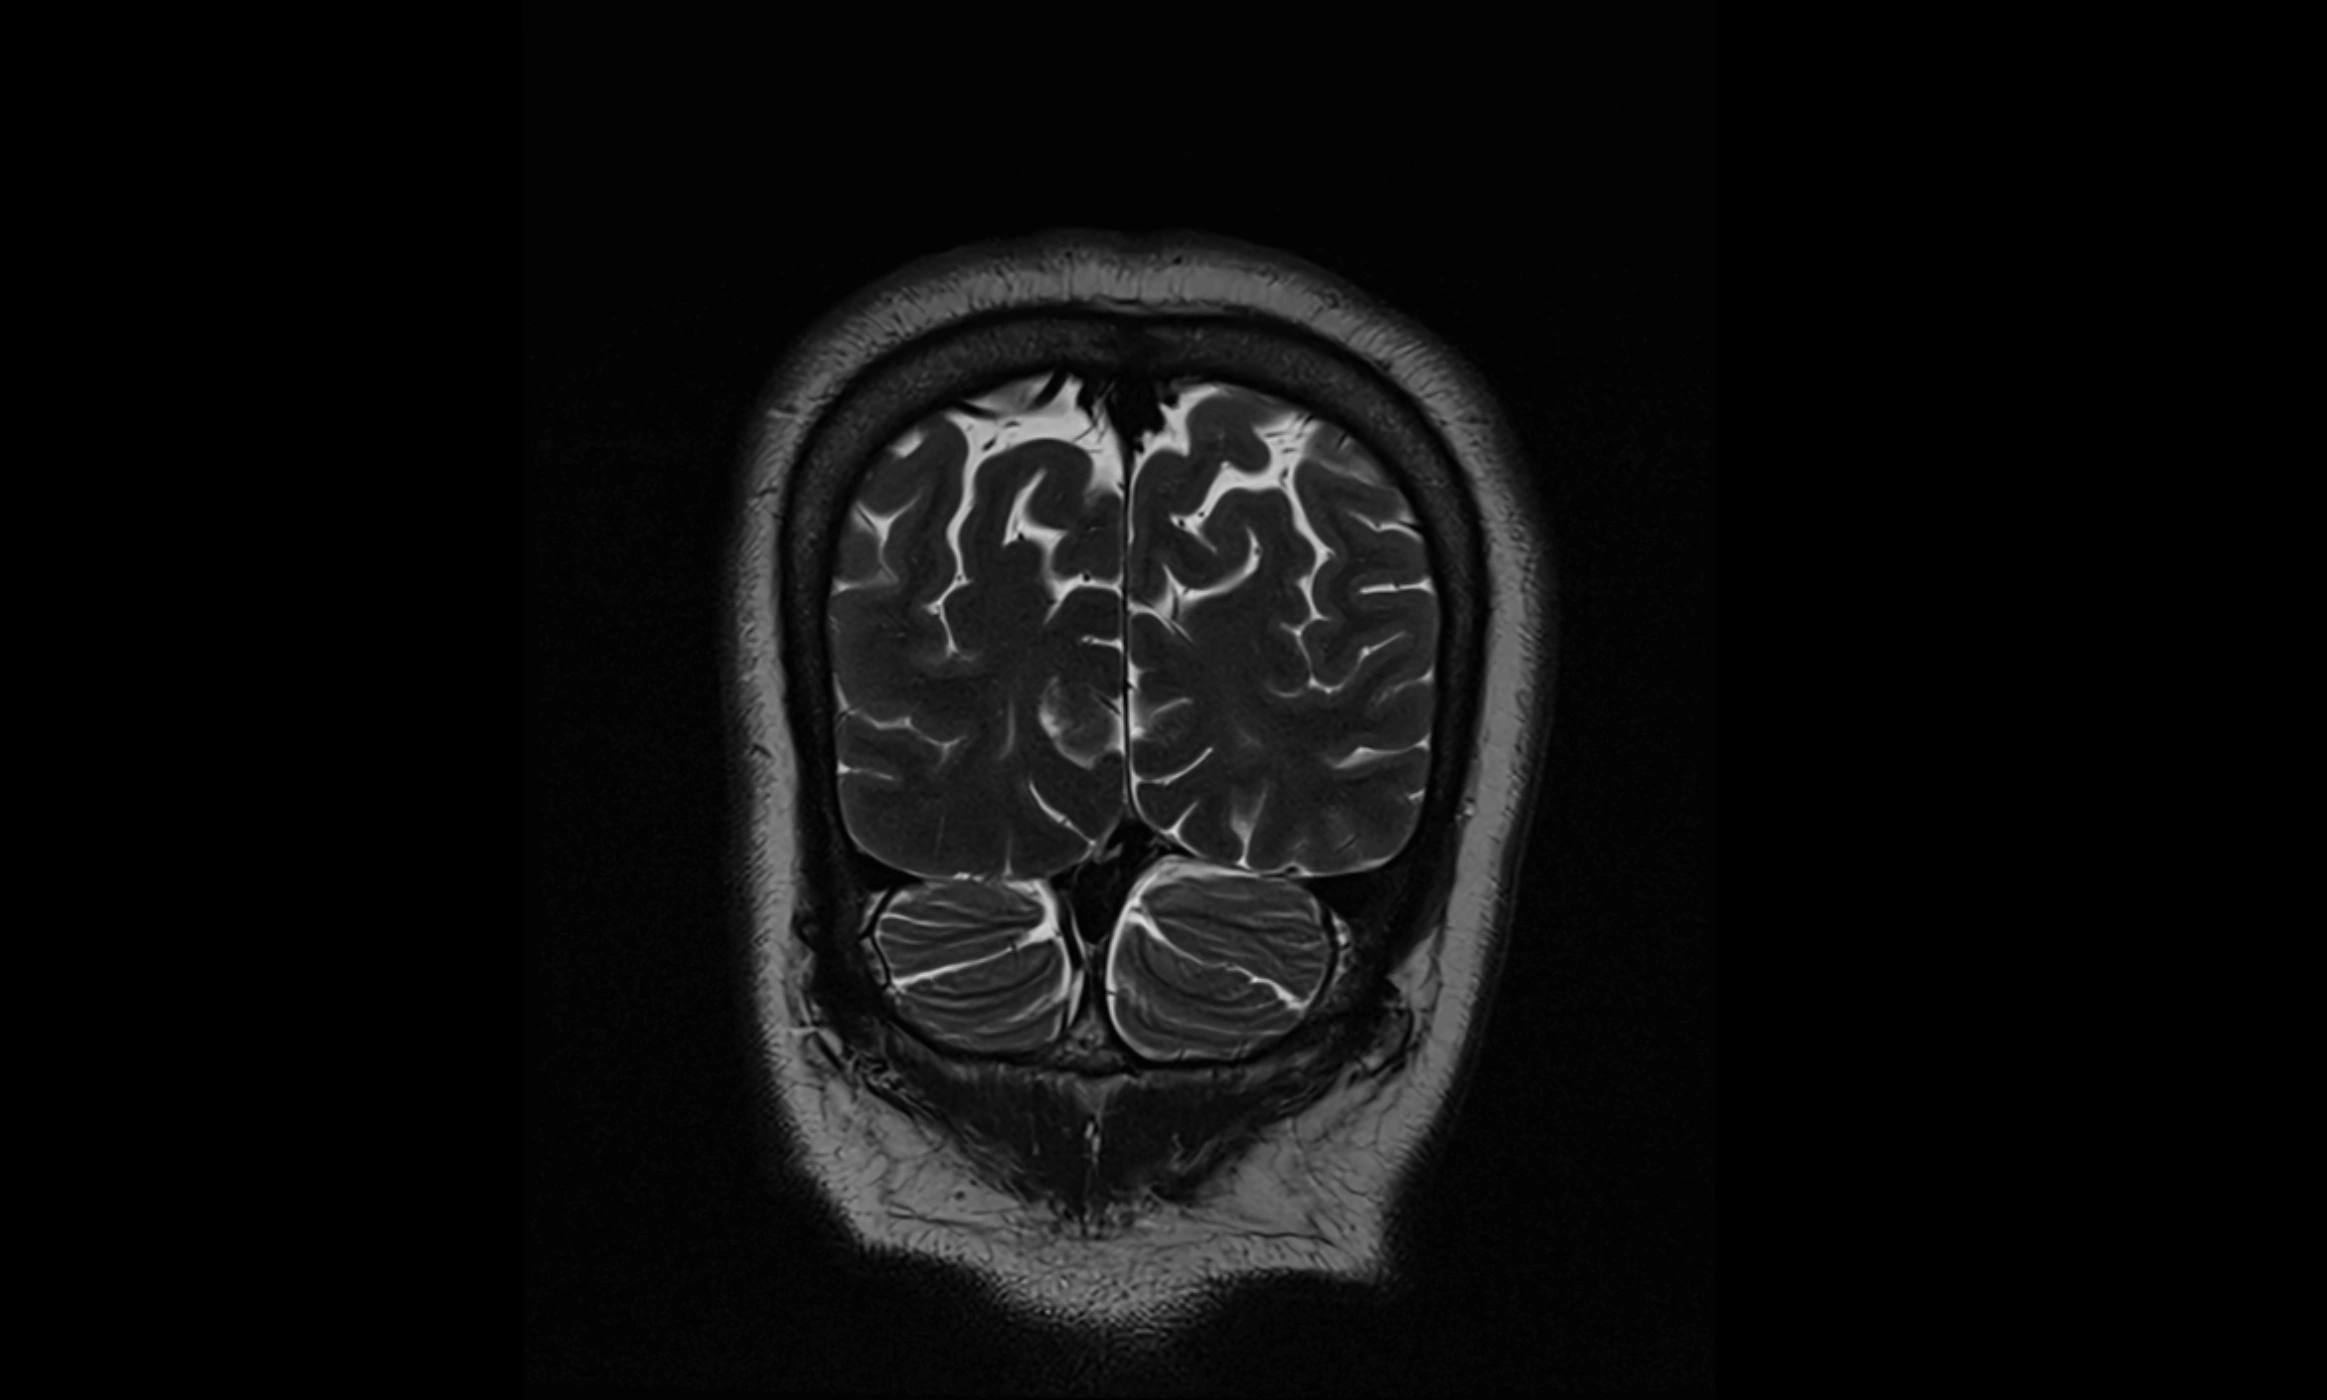

MRI images

image